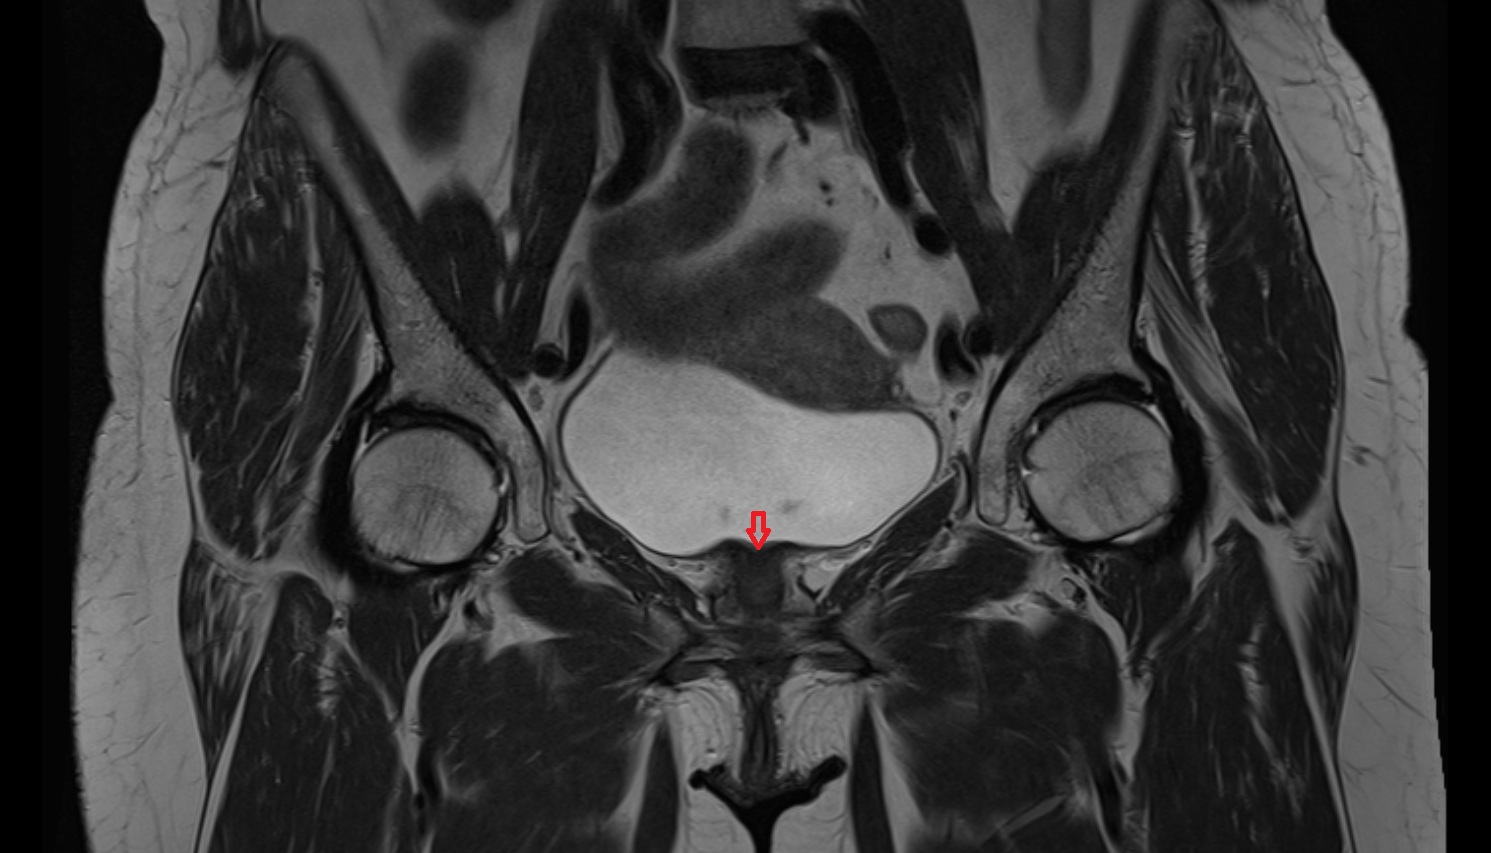

- Uterus

- Body of uterus

- Fundus of uterus

- Cervix of uterus

- Isthmus of uterus

- Vagina

- Endometrium of uterus

- Myometrium of uterus

- Junctional zone of uterus